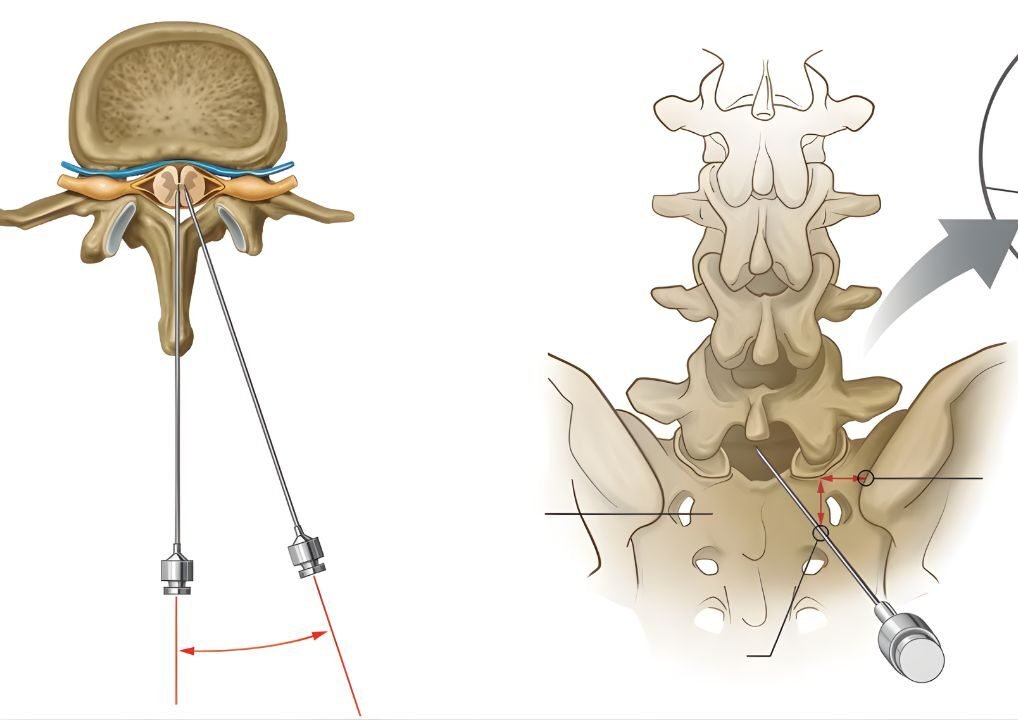

Não. Nossa filosofia prioriza procedimentos minimamente invasivos. A grande maioria dos casos é resolvida com intervenções percutâneas (sem cortes), terapias medicamentosas ajustadas, ondas de choque ou infiltrações guiadas. A cirurgia é considerada apenas quando estritamente necessária.

São técnicas onde utilizamos ultrassom ou radioscopia em

tempo real para guiar agulhas e instrumentos com precisão milimétrica até o alvo da dor. Isso garante maior segurança e eficácia.